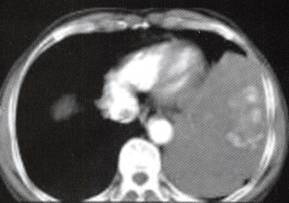

图1胸膜孤立性纤维瘤

A

B

C

D

A.B.CT平扫示左中下胸巨大肿块,宽基底与胸壁相连,内见斑片状钙化;

C~F.CT增强扫描肿块内缘肺门侧见一血管蒂样结构与纵隔相连,中度不均匀强化,内见匍行、紊乱的血管影,肿块中度均匀强化;